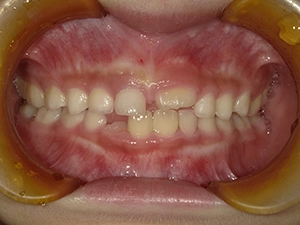

実際に小野歯科医院で行っているマイオブレースを用いた小児矯正の症例を紹介します。

どんどんきれいな歯並びになっていく様子を一緒に確認していきましょう!

治療前

| 術名 | マイオブレース矯正 |

|---|---|

| 年齢 | 6歳 |

| 性別 | 男性 |

| 主訴 | 下の前歯のガタつきが気になる |

| 診断名 | 叢生 |

| 治療内容 | マイオブレース矯正 |

| 治療期間 | 治療開始2ヶ月時点での変化 |

| 費用 | 基本料33万(検査診断料.月々の調整料別途) |

| リスク・副作用 | 特になし |